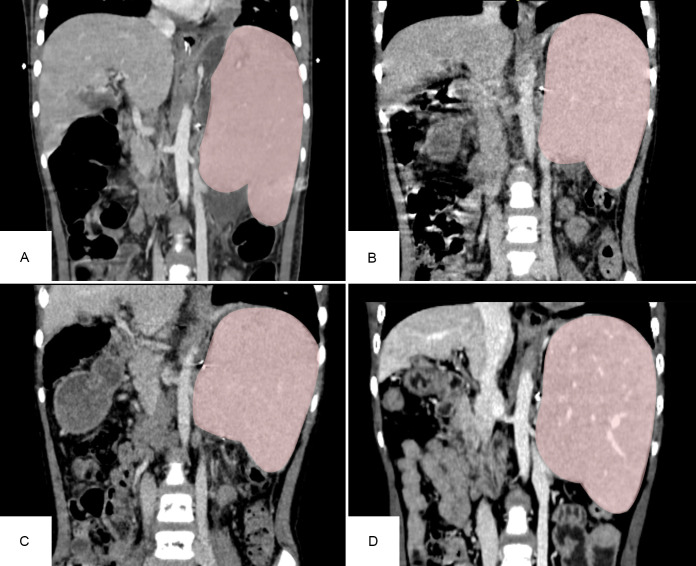

Heterotopic Auxiliary Liver Transplantation in a Child with Portal Hypertension Using a Discarded Partial Right Liver Allograft from an Adult Patient with Alveolar Echinococcosis.

异位辅助性肝移植治疗门脉高压症患儿使用成人肺泡包虫病患者丢弃的部分右同种异体肝。